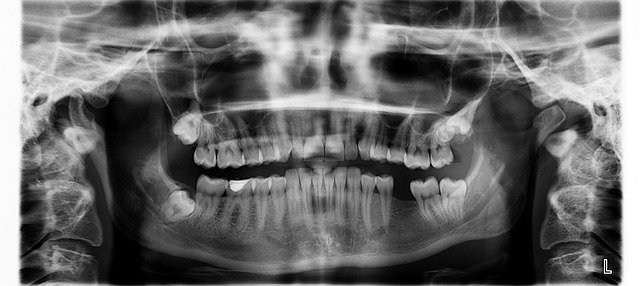

La endodoncia, también llamada popularmente matar el nervio, es una intervención del dentista que evita tener que extraer la pieza dañada, pudiendo conservar esta y mantener su funcionalidad.

Esta práctica se puede realizar por varios motivos, pero alguno puede ser el dolor de muelas causado cuando las caries son muy profundas, o por hipersensibilidad.